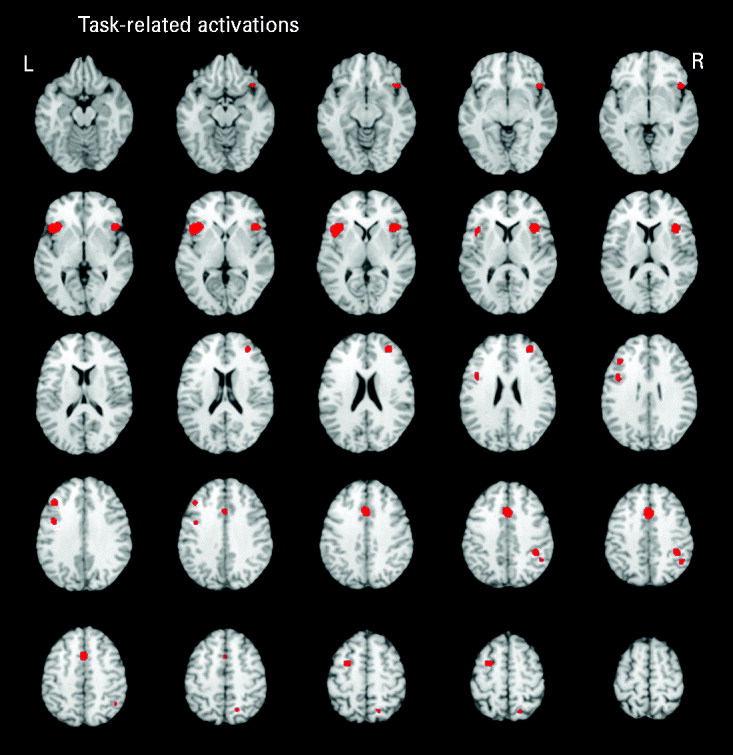

Five studies reported executive functioning task-related activity combined across relatives and control groups. Robust activations were found in 10 clusters, encompassing the bilateral middle frontal (BA 9/10), bilateral inferior frontal (BA 9/47), anterior cingulate (BA 32), bilateral insula (BA 13), left precentral (BA 6), right inferior parietal (BA 40) and right superior parietal (BA 7) regions (see Fig. 1).

Fig. 1. Above-threshold brain activations associated with executive functioning for both the control and relative groups combined. L, left; R, right.